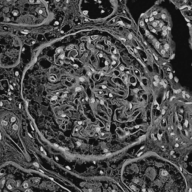

Image datasets in digital pathology applications often consist of consecutive slides stained differently, each staining providing specific information on the same region of interest (see Figure 1, first row). Even though differently stained slides appear very different, there is often a significant amount of consistent information between them. For example, they may both share the same counterstain (e.g. haematoxylin), or they may highlight different parts of the same structure.

Objects to be segmented, e.g. glomeruli, are generally easily identified between stainings as globally they exhibit the same structure and texture, see Figure 1. It should therefore be possible to bias the network to learn stain invariant features. This work investigates this possibility by modifying the data presented to the network in an unsupervised manner. Borrowing domain adaptation terminology, herein the staining used for training and validation is referred to as as the source staining (irrespective of any transformations), and the stainings to which the network are applied as target stainings.

Next is a strategy to extract biological information that is consistent across different stainings—the haematoxylin counterstain. Despite this biological plausibility, it does not result in good results. Indeed, the haematoxylin transformed images vary greatly between the different stainings (see Figure 1, second row). Several factors may explain this: 1) haematoxylin’s concentration relative to the primary stain may vary from one staining to another, resulting in different shades of blue and fixation amount; 2) as a counterstain, haematoxylin may become mixed with another stain in structures that are targeted by both. These result in a color mixing that is in practice not perfectly unmixed by a color deconvolution algorithm.